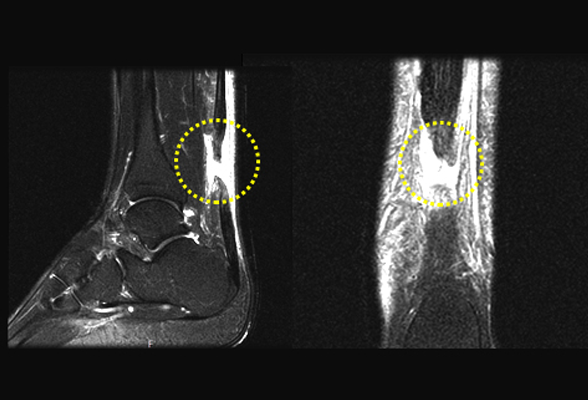

아킬레스 건염

아킬레스 건염이 지속되어 아킬레스건이 파열되거나 외부의 충격 등

다양한 원인에 의해 아킬레스건이 끊어지는 것을 말합니다.

비수술 치료 : 약물, 고정 (깁스 또는 보조기), 물리치료, 주사치료, 도수치료

수술치료 : 아킬레스건 봉합술